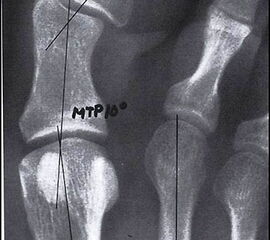

Abbildung 1

Nach Anamneseerhebung stellen die klinische Untersuchung und die Durchführung von belasteten Röntgenaufnahmen in zwei Ebenen die wesentlichen Pfeiler für die spätere Operationsplanung dar. Bei der Inspektion können Begleitpathologien detektiert werden wie z.B. plantare Schwielenbildung unter dem Metatarsale-II-Köpfchen

(Abb. 1) als Ausdruck einer Überlastung des 2. Strahles oder aber Schwielenbildungen im Bereich der Beere der Großzehe bei Torsionsfehlstellungen und eingeschränkter Beweglichkeit des Großzehengrundgelenkes. Die typische Fehlstellung der Großzehe selbst im Sinne eines Hallux valgus interphalangeus am Grundglied ist ebenfalls oft nachzu weisen. Im Falle einer Rigiduskomponente liegt die knöcherne Prominenz am Köpfchen des 1. Mittelfußknochens eher dorsalseitig. Bei der Palpation können spezifische Schmerzpunkte gefunden werden. Bei der Beweglichkeitsprüfung deuten Einschränkungen der normalen Dorsalextension von 70-90° passiv auf beginnende arthrotische Veränderungen hin, die Beweglichkeitsprüfung des Endgelenkes dient zum Ausschluss von degenerativen Veränderungen auch in diesem Gelenk. Für die Wahl des Operationsverfahrens entscheidend ist die im Video beschriebene Stabilitätsprüfung: Um dem funktionellen Aspekt der stabilisierenden Muskulatur Rechnung zu tragen, prüfen wir bei der klinischen Untersuchung die Mobilität des 1. Strahles, durch Testen der relativen Beweglichkeit des Metatarsale I gegenüber den kleineren Metatarsalia, einmal im entspannten Zustand und anschließend nachdem der Patient aktiv die Peronealmuskulatur durch Anheben des lateralen Fußrandes angespannt hat (Abb. 2 u. Abb. 3) (Video 1).